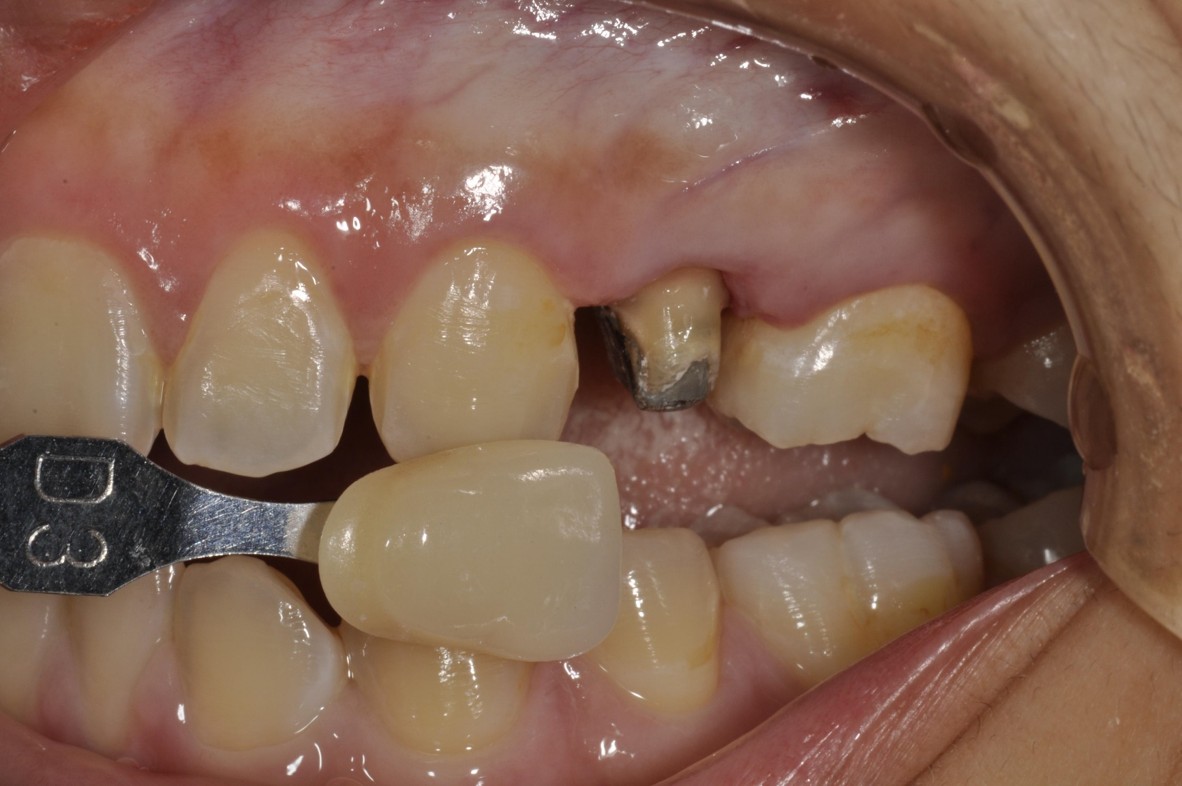

膺復前評估牙齦、牙齒狀態

照相比色